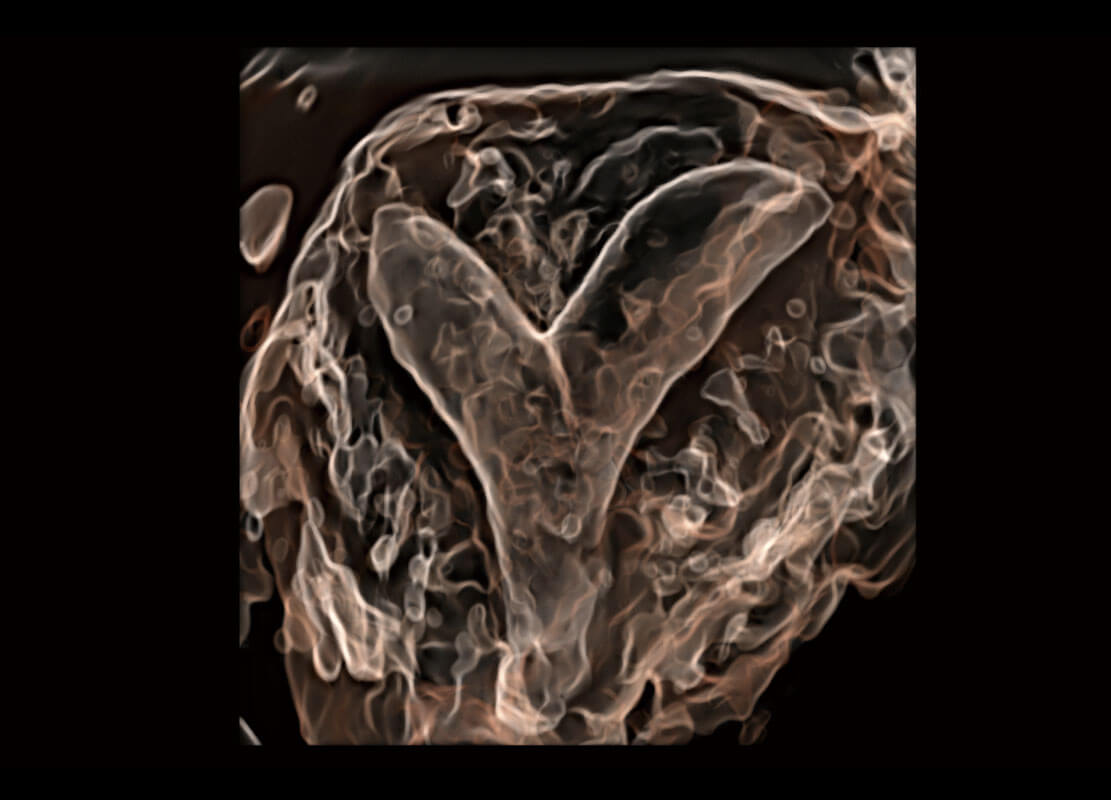

腔内三维-宫内节育器

腔内三维-光影成像